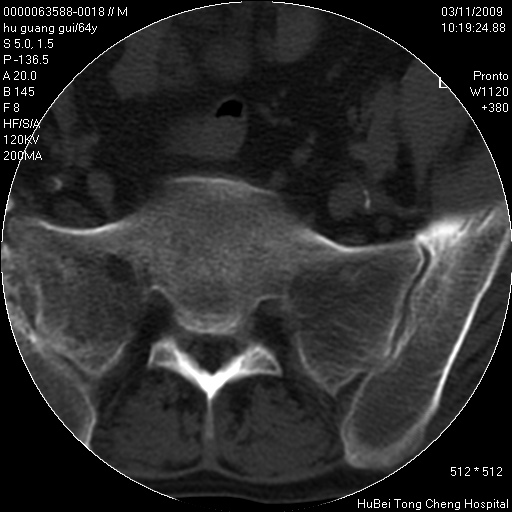

患者 男,64岁。腰痛十余天。(临床未提供其他病史)

临床诊断:腰痛原因待查(腰椎间盘突出症?)。

腰椎间盘ct轴位平扫(层厚5mm,层距4mm),图像如下:

右侧骶骨侧块骨侵蚀,骶髂关节骨性关节面破坏,并见软组织肿块,考虑骨转移瘤可能,进一步检查。

1.腰椎退行性变,腰4—5椎间盘膨出。

2.右侧骶骨侧块骨侵蚀,骶髂关节骨性关节面破坏,并见软组织肿块,考虑:脊索瘤,骨转移瘤可能,进一步检查。

1)腰椎退行性变,l4—5椎间盘膨出。2)骶骨右侧块骨转移瘤可能,3)水平骶椎。建议作一步检查。